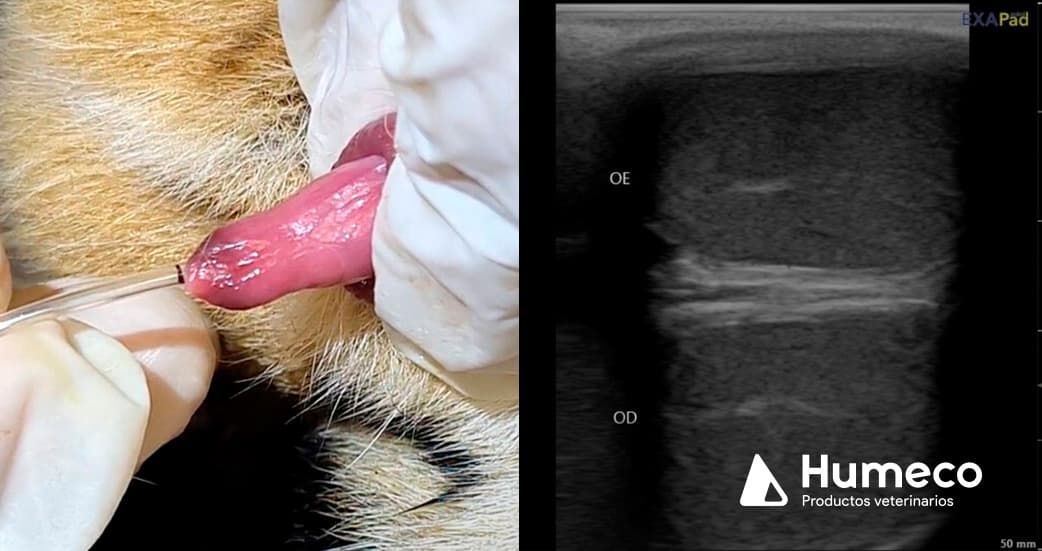

Este grupo de investigación tiene el objetivo de desarrollar biotecnologías reproductivas para la conservación de especies silvestres, y en este estudio ecografió los testículos de jaguares machos adultos usando el ecógrafo Exapad Mini, de IMV Imaging, y analizó las imágenes obtenidas usando el software Ecotext. Simultáneamente, se recolectó el semen a través de cateterismo uretral, y los espermatozoides fueron evaluados por CASA.

En el estudio preliminar se observa la misma pauta que la obtenida en otras especies: animales con mejor calidad seminal presentan una mayor densidad de áreas hipoecogénicas en la ecografía del parénquima testicular.